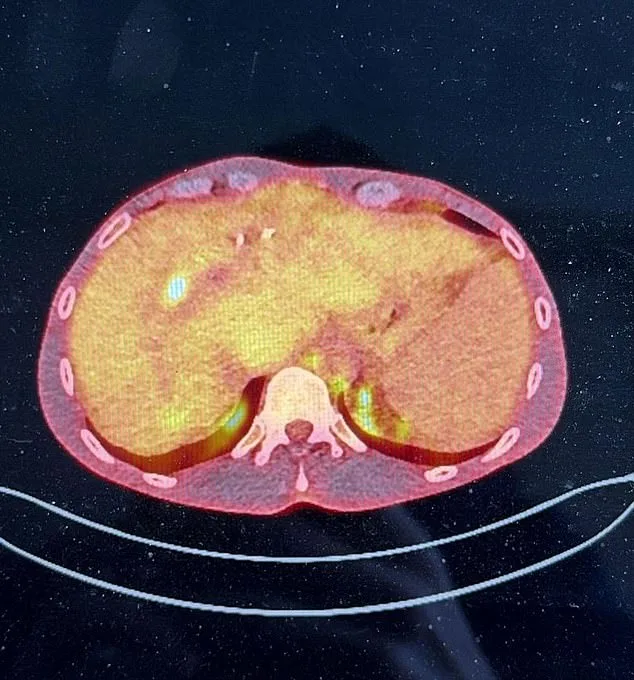

People with primary sclerosing cholangitis are more likely to develop liver cancer, with six to 15 per cent being diagnosed with cholangiocarcinoma. There are around 3,100 cases of PSC diagnosed in the UK annually. A CT PET scan showed a 2.4cm tumour in James's liver, a critical detail in his case.